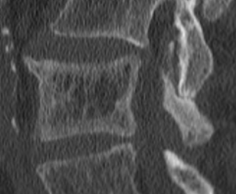

Picture Frame sign

- Epaississmeent cortical en cadre des vertèbres

- Pas juste le haut et le bas comme dans l’hyperparathyroidisme

vertèbres en cadre image Blade of Grass / Brin d’herbe / Candle Flame Signbanane enOstéodystrophie déformante osseux osteodytrophie